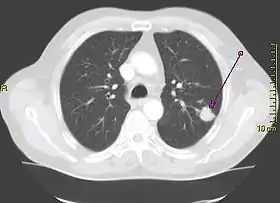

A person suspected of having lung cancer will have imaging tests done to evaluate the presence, extent, and location of tumors. First, many primary care providers perform a chest X-ray to look for a mass inside the lung.[8] The X-ray may reveal an obvious mass, the widening of the mediastinum (suggestive of spread to lymph nodes there), atelectasis (lung collapse), consolidation (pneumonia), or pleural effusion;[9] however, some lung tumors are not visible by X-ray.[5] Next, many undergo computed tomography (CT) scanning, which can reveal the sizes and locations of tumors.[8][10]

Lung cancer can often appear as a solitary pulmonary nodule on a chest radiograph or CT scan. In lung cancer screening studies as many as 30% of those screened have a lung nodule, the majority of which turn out to be benign.[15] Besides lung cancer many other diseases can also give this appearance, including hamartomas, and infectious granulomas caused by tuberculosis, histoplasmosis, or coccidioidomycosis.[16]